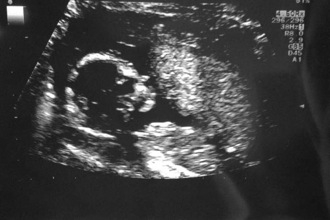

Ultraschall mit Folgen - Tagebücher aus der Schwangerschaft von Ophelia aus Köln